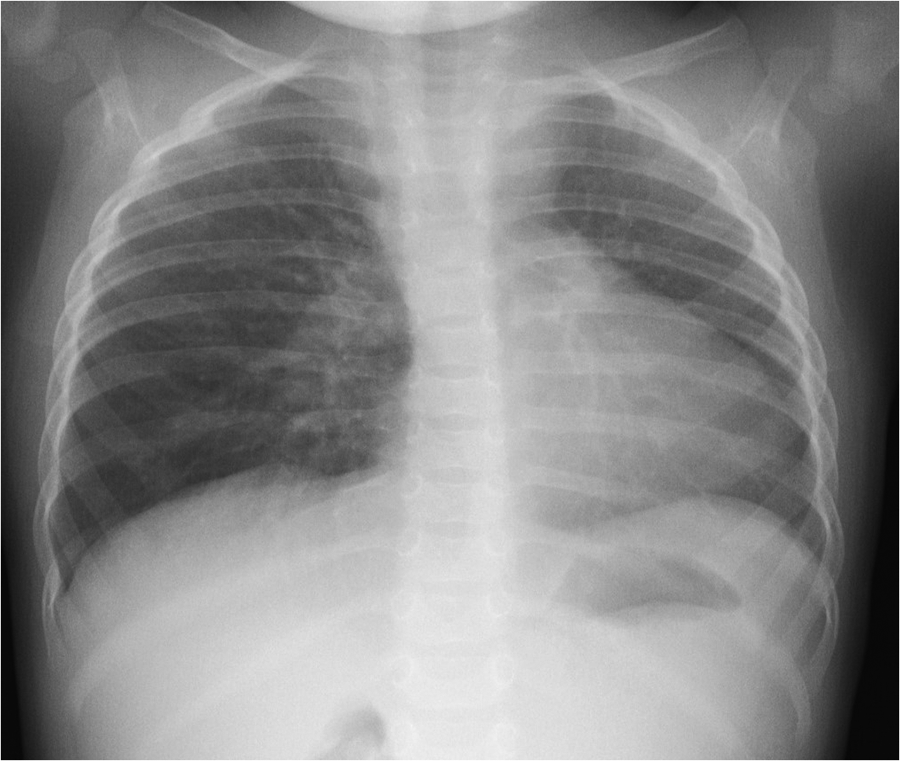

A 1-year-old girl presented to the emergency department with cough and variable wheezing, which started as an upper respiratory tract infection and persisted for two weeks after the other symptoms of the infection had resolved. She was otherwise healthy. No specific details of the personal or family history were clarified. The patient did not have tachypnea or tachycardia; pulse oximetry was normal on room air, but she had mild to moderate wheezing, expressed mainly during physical activity and not observed during sleep. Lung auscultation revealed bilateral crackles and variable, high-pitched, whistling sounds during exhalation. No other pathological findings were noted on clinical examination. Inhaled salbutamol was ineffective. Chest radiographs showed a decreased volume of the left lung, shifting of the mediastinum to the left, and enlargement of the right lung hilum (Figure 1).

Figure 1. Chest radiograph image: decreased volume of the left lung, shifting of the mediastinum to the left, enlargement of the right lung hilum.

Heart and mediastinal displacement, ipsilateral elevation of the diaphragm, and contralateral hyperinflation are observed on chest radiographs in patients with isolated UPAA, whereas KD can only be diagnosed after chest CT or magnetic resonance imaging (MRI) (1, 3–6). Similar abnormalities of UPAA on chest radiography were observed in our patient. An abnormal x-ray scan led to a detailed examination. A transthoracic echocardiogram revealed the absence of the left pulmonary artery and was suspicious for malformations of the aortic arch vessels. Other researchers also reported cases of asymptomatic UPAA incidentally suspected after abnormal findings in the chest x-ray image (3, 4). A contrast-enhanced chest CT scan was sufficient to confirm the diagnosis of left UPAA, and it enabled us to detect an asymptomatic, extremely rare type of KD (1, 3, 4). Chest MRI or ventilation-perfusion scintigraphy can also be used to diagnose UPAA (1).